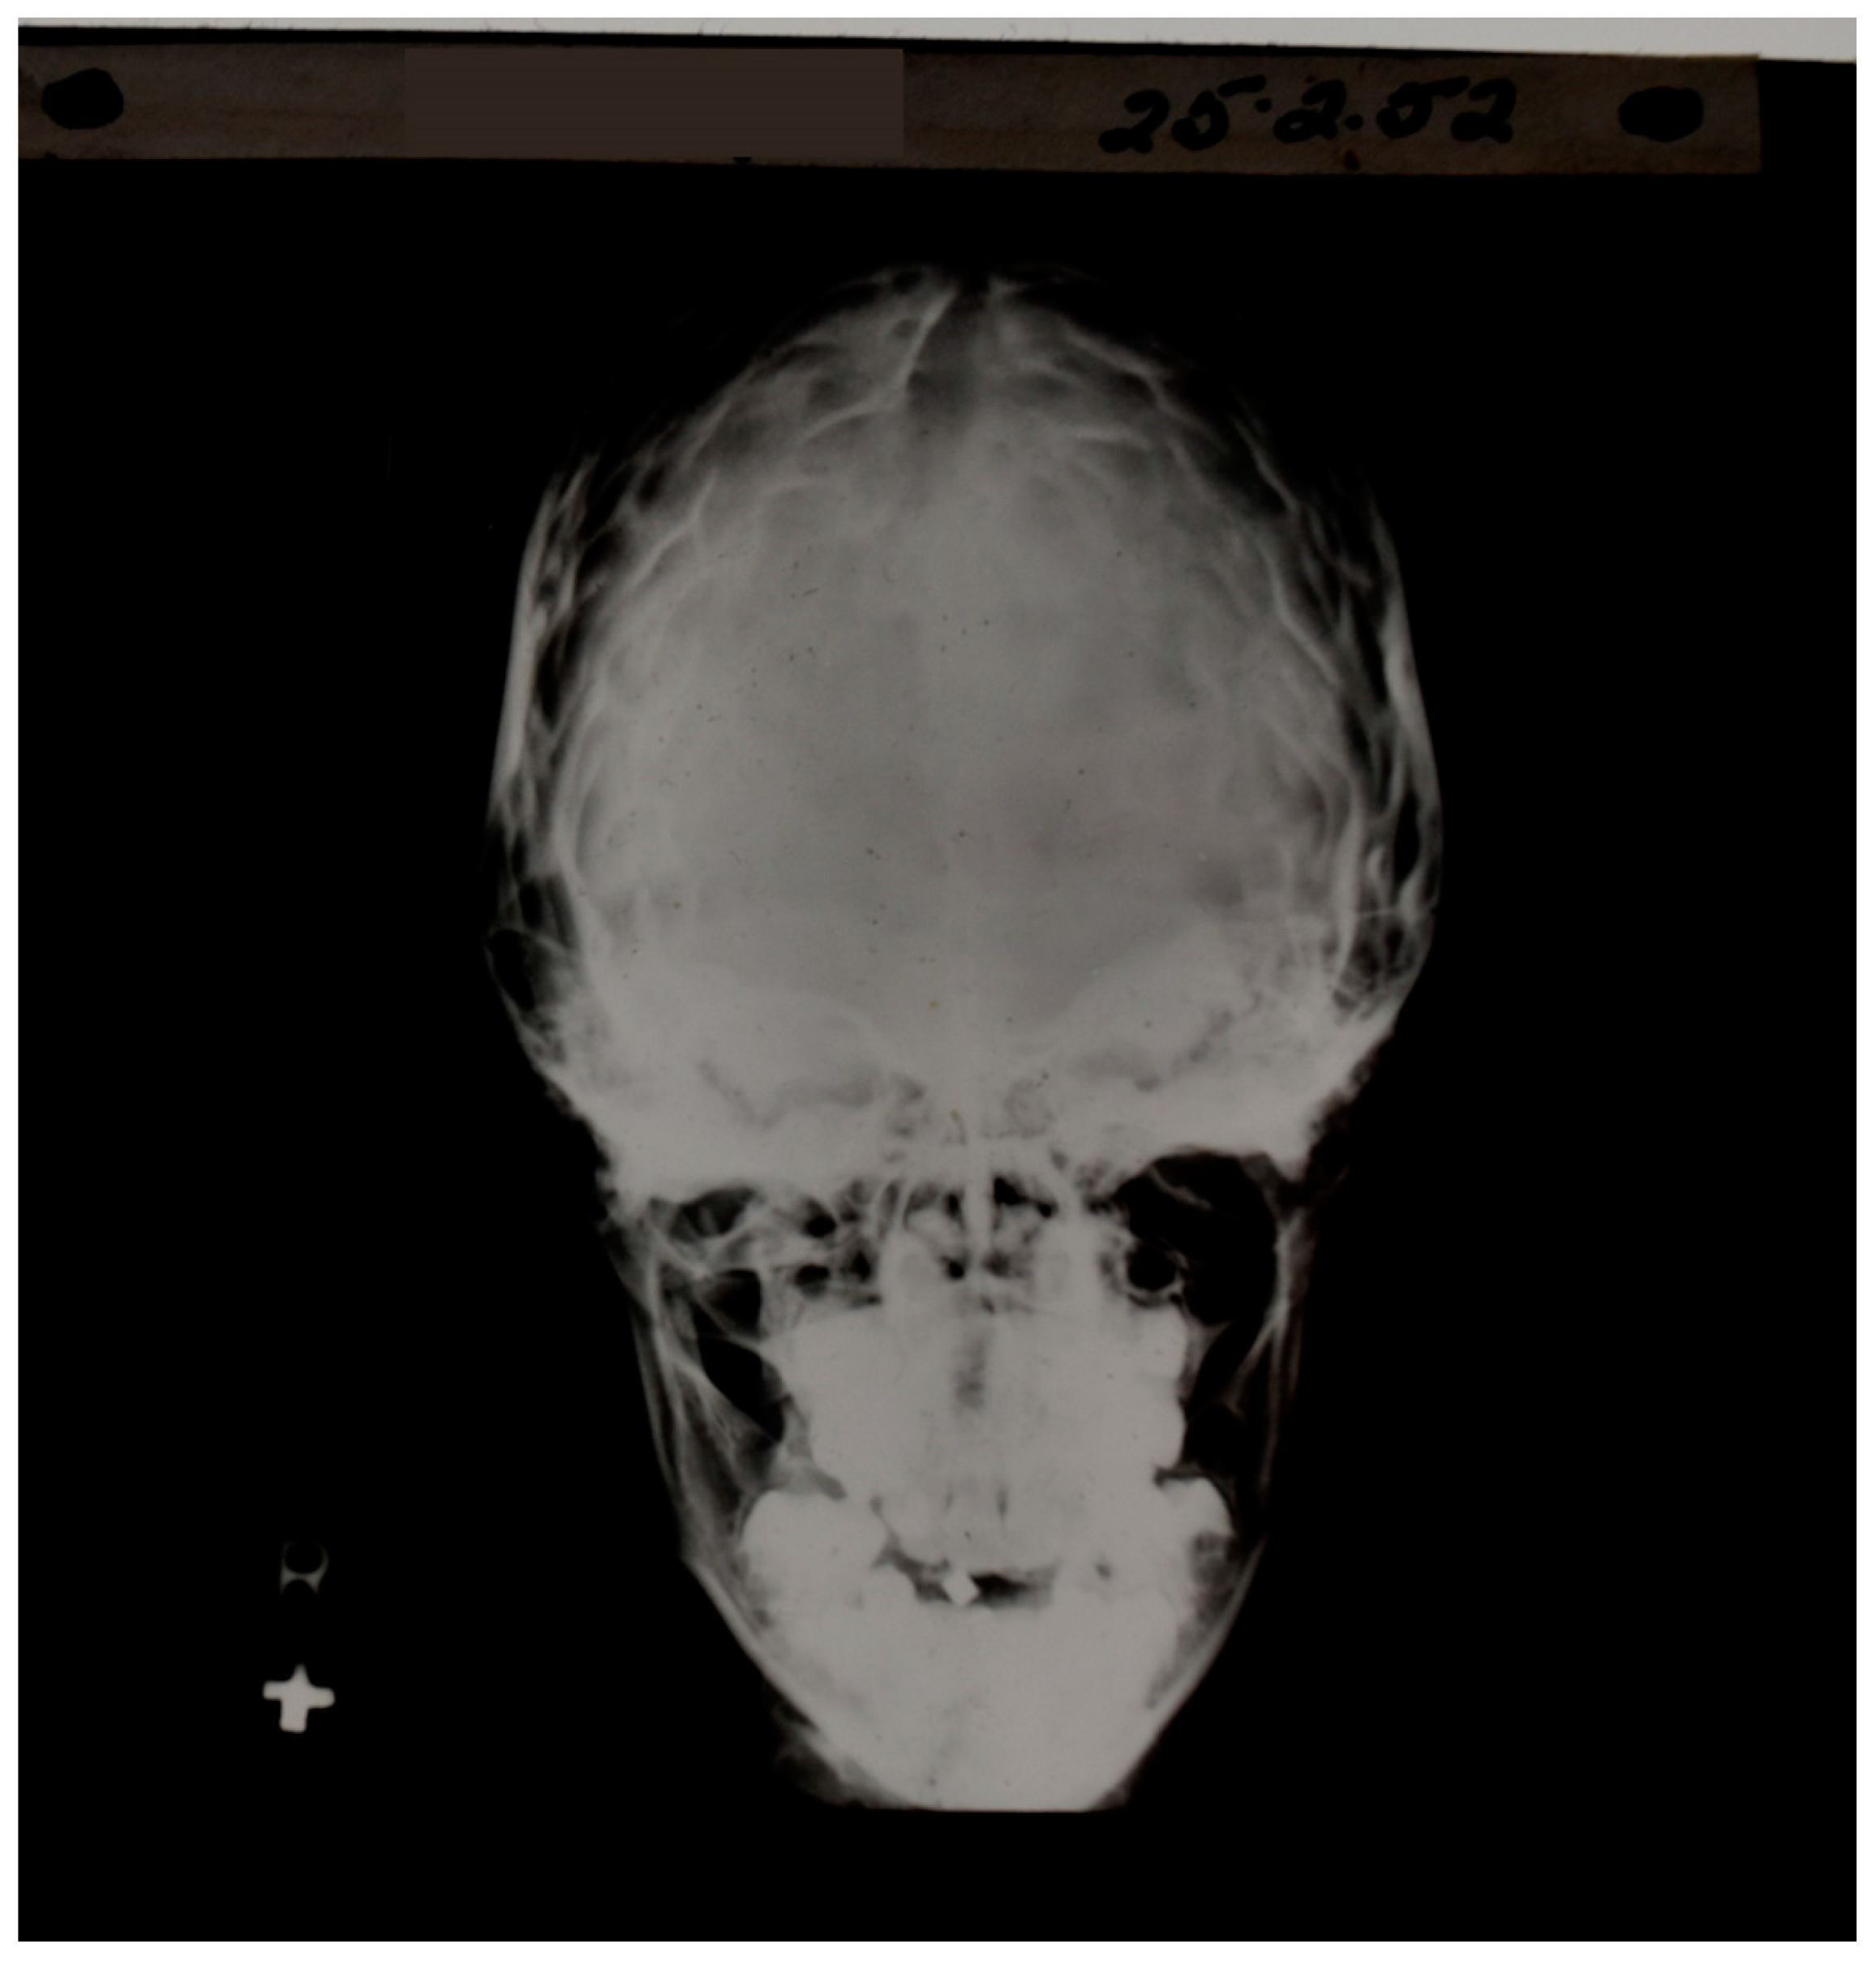

Figure 2.

Early skull X-ray. Contrast is seen between bone and air as well as between bone of different thicknesses; however, the soft tissue of the brain is not directly observable.